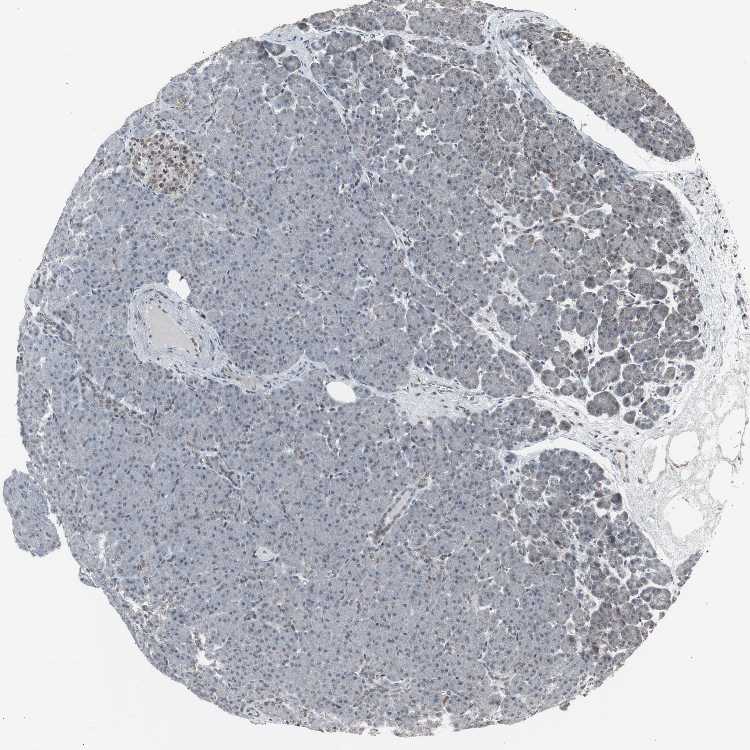

PANCREAS - Antibody stainingi

Antibody staining in the annotated cell types in the current human tissue is reported as not detected, low, medium, or high, based on conventional immunohistochemistry profiling in selected tissues. This score is based on the combination of the staining intensity and fraction of stained cells.

Each image is clickable and will lead to virtual microscopy that enables deeper exploration of all samples and also displays staining intensity scores, fraction scores and subcellular localization as well as patient and tissue information for each sample.

Antibody CAB004565Antibody CAB005352

Exocrine glandular cells HighNot detected

Pancreatic endocrine cells HighLow